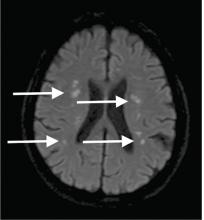

Although CT may underestimate osmotic demyelination syndrome, the typical radiologic findings on brain MRI are hyperintense lesions in the central pons or associated extrapontine structures on T2-weighted and fluid-attenuated inversion recovery sequences.4

Our patient’s clinical course and high hemoglobin A1c suggested prolonged hyperglycemia and high serum osmolality before his admission. After his admission, aggressive hydration and insulin therapy corrected the hyperglycemia and serum osmolality too rapidly for his brain cells to adjust to the change. It was reasonable to suspect a hyperosmolar hyperglycemic state as one of the main causes of his mental status change and ataxia. This, along with lack of improvement in his impaired metal status and new-onset ataxia despite treatment, led to suspicion of osmotic demyelination syndrome. His diminished bilateral knee-jerk and ankle-jerk responses more likely represented diabetic neuropathy rather than osmotic demyelination syndrome.

There is no specific treatment for osmotic demyelination syndrome except for supportive care and treatment of coexisting conditions. Once an osmotic derangement is identified, we recommend correcting chronically elevated serum glucose values gradually to avoid overtreatment, just as we would do with elevated serum sodium levels. Changes in neurologic findings, serum blood glucose level, and serum osmolality should be followed closely. A review showed that a favorable recovery from osmotic demyelination syndrome is possible even with severe neurologic deficits.4